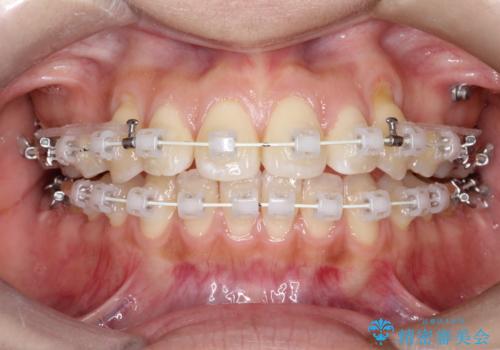

- 矯正装置

- 審美装置

- 前歯の凸凹を主訴に来院されました。

予想治療期間2年でしたが、実際は1年半ほどで終了し満足していただきました。

小臼歯抜歯(上顎4番)して矯正治療を行なったことで、口元もスッキリしました。